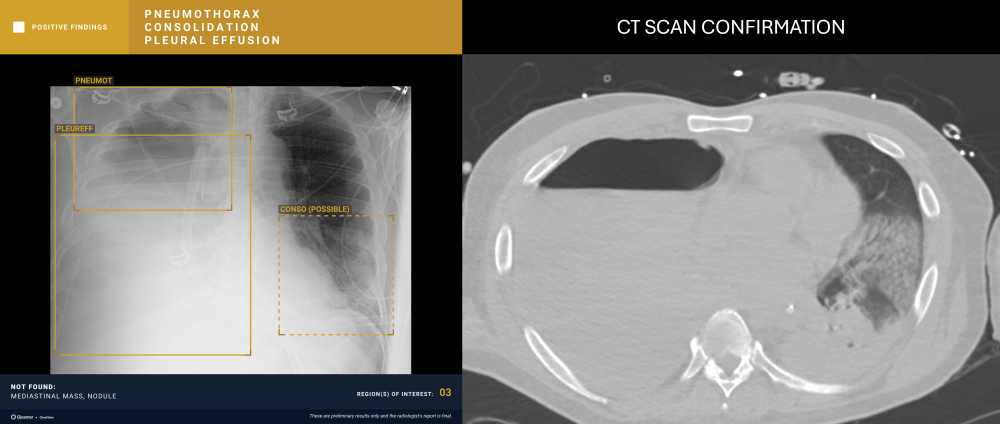

A 54-year-old male with respiratory difficulty.

ChestView detected an infectious region in the right lower lobe and incidentally identified left hilar lymphadenopathy